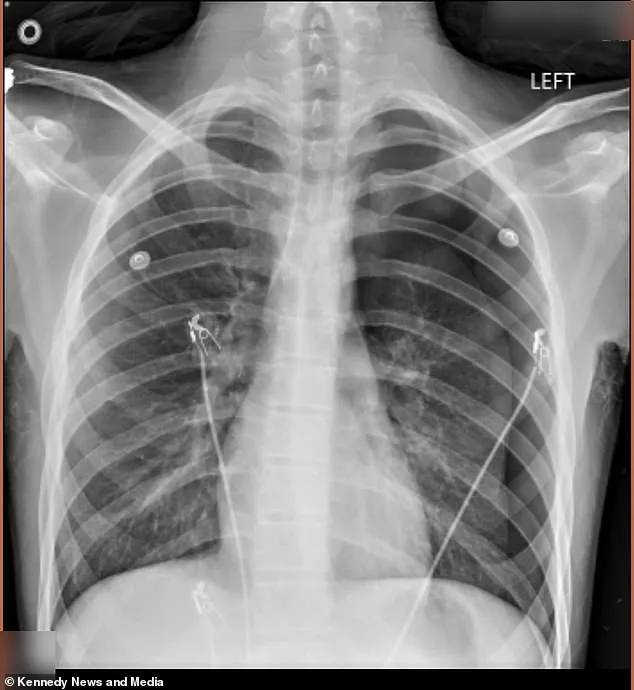

A Kentucky mother is issuing a stark warning after her teenage son's life was turned upside down by a dangerous habit he adopted to fit in with his peers. Cameron Vann, known as Dodge, began vaping two years ago to appear 'cool' in front of his friends, but he kept the secret from his mother, Crystal Vann, until it was too late. In September 2025, Dodge emerged from the school bus pale and in severe pain, prompting Vann to rush him to the emergency room. A chest x-ray revealed that 50 percent of his left lung had collapsed, a condition known as a pneumothorax, which occurs when air enters the chest cavity and exerts pressure on the lung.

The severity of the situation forced doctors to perform a surgical intervention, inserting an 18-inch tube into Dodge's chest to remove the excess air and allow his lung to re-expand. However, the teenager continued to vape in secret, unaware of the long-term consequences of his actions. It wasn't until January 2026 that Dodge once again called his mother, out of breath and in intense pain, signaling the recurrence of the condition. This time, the situation was even more dire. Doctors warned that if they hadn't acted quickly, Dodge could have died in the hospital lobby.